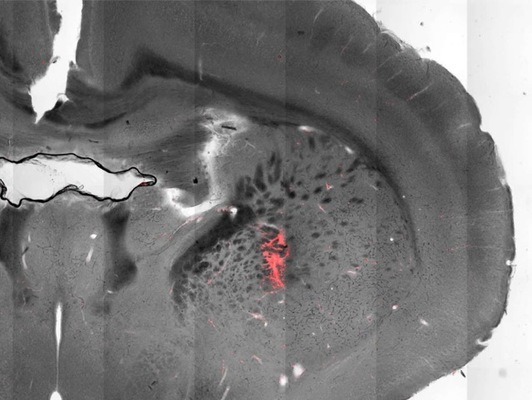

El tratamiento TMS implicó una serie de pulsos magnéticos de alta frecuencia de 20 Hz durante dos sesiones al día durante dos días. Mediante resonancia magnética (IRM), los pulsos se dirigieron a un área cerebral específica en el lóbulo temporal, asociada con el lenguaje (el área exacta es el cruce de la proyección de la rama ascendente del surco lateral izquierdo y el surco temporal superior izquierdo).